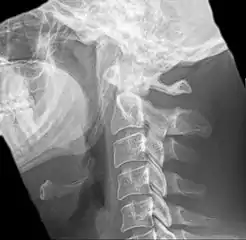

| Anteroposterior and lateral radiographs of cervical spine showing ossification of the stylohyoid ligament on both sides | |

Eagle syndrome (also termed stylohyoid syndrome,[1] styloid syndrome,[2] styloid-stylohyoid syndrome,[2] or styloid–carotid artery syndrome)[3] is an uncommon condition commonly characterized but not limited to sudden, sharp nerve-like pain in the jaw bone and joint, back of the throat, and base of the tongue, triggered by swallowing, moving the jaw, or turning the neck.[1] First described by American otorhinolaryngologist Watt Weems Eagle in 1937,[4] the condition is caused by an elongated or misshapen styloid process (the slender, pointed piece of bone just below the ear) and/or calcification of the stylohyoid ligament, either of which interferes with the functioning of neighboring regions in the body, such as the glossopharyngeal nerve.[4]

Eagle syndrome occurs due to elongation of the styloid process or calcification of the stylohyoid ligament, potentially compressing the nearby carotid arteryor glossopharyngeal nerve.[4] However, the cause of the elongation hasn’t been known clearly. It could occur spontaneously or could arise since birth. Usually normal stylohyoid process is 2.5–3 cm in length, if the length is longer than 3 cm, it is classified as an elongated stylohyoid process.[10] There are reports of eagles syndrome been elicited after wisdom tooth removal. [11]